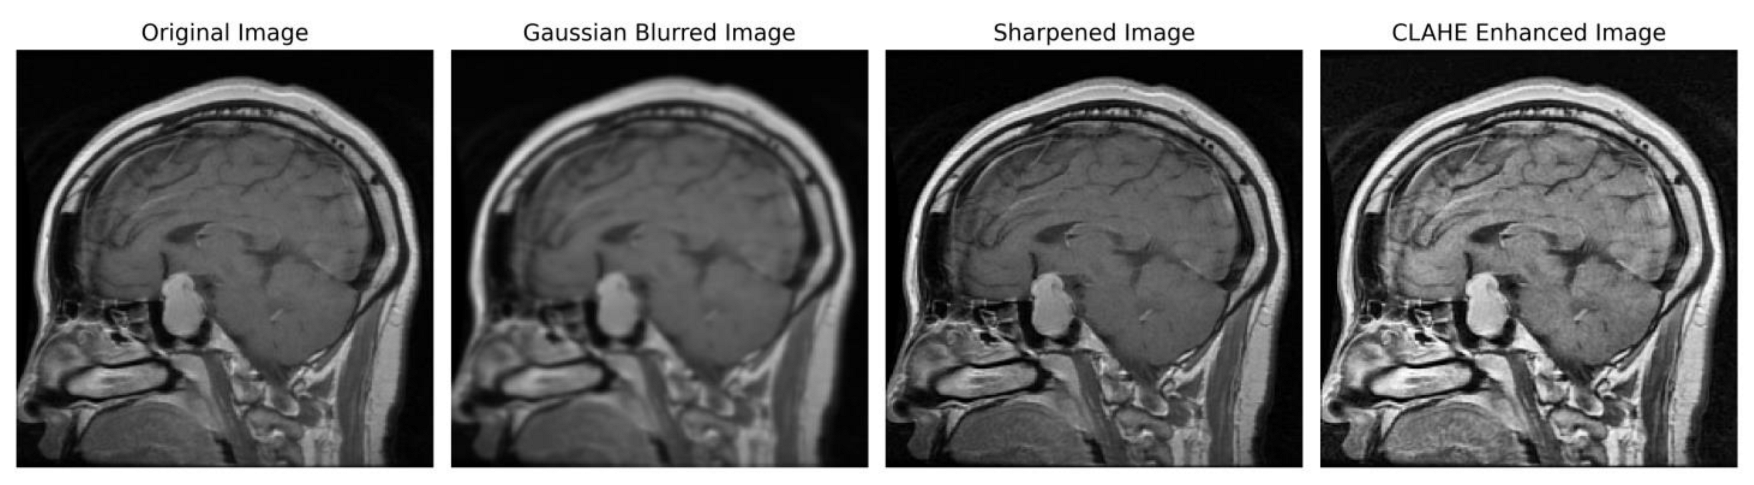

We implemented a preprocessing framework to improve image quality by integrating sharpening and Contrast-Limited Adaptive Histogram Equalization (CLAHE) approaches. The process of sharpening commenced by implementing a Gaussian blur through the utilization of a specific technique. The utilization of a 5 × 5 kernel was suitable in the process of attenuating high-frequency noise. The resultant enhanced image was determined using the formula:

S h a r p e n e d   I m a g e = 1.5 × O r i g i n a l   I m a g e 0.5 × B l u r r e d   I m a g e

Subsequently, the image underwent a conversion process to grayscale, facilitating a precise enhancement of contrast. To achieve this, CLAHE was utilized, characterized by an 8 × 8-tile grid and a clip limit of 2.0. Distinct from global histogram equalization, CLAHE adopts a localized strategy by partitioning the image into discrete tiles and performing individual equalizations, encapsulated by

H l o c a l ( i ) = C L A H E ( H t i l e ( i ) )

In order to ensure accordance with the specifications of the subsequent deep learning framework, the enhanced grayscale image was transformed into the RGB color space [49,50]. Figure 3 illustrates the several stages of enhancing picture quality, from the initial image to the CLAHE-enhanced image. This depiction showcases the effectiveness of our preprocessing method and its notable impact on improving the overall quality of the image.

Figure 3. Sequential image improvement as part of the preprocessing framework. The stages progress from the unaltered original image through Gaussian blurring for noise suppression, sharpening the emphasized edge definition to the final enhancement using CLAHE.